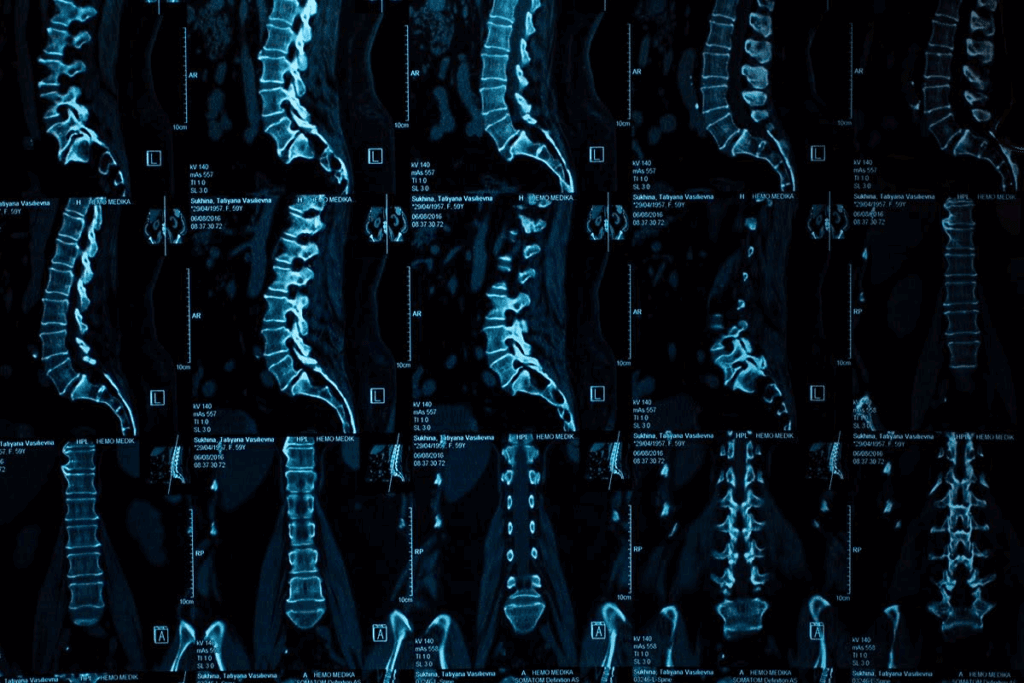

CT Scan Herniated Disc Detection Capabilities

CT scans use X-rays to create detailed images of the body. They are great at finding herniated discs. This makes them a key tool for diagnosing spinal problems.

CT Scan Technology Explained

CT scans combine X-rays from different angles to show cross-sections of the body. This lets us see the spine’s details, like vertebrae and discs. It’s fast and doesn’t hurt, making it a great tool for doctors.

CT scans are good at showing both bones and soft tissues. This helps doctors spot herniated discs. These discs can press on nerves if they bulge out.

How CT Visualizes Spinal Structures

CT scans are great at showing the spine’s bones, like vertebrae and joints. They also give info on discs, but might miss soft tissue details. The images can show disc herniations and other problems.

When a CT scan looks for disc herniation, a radiologist checks the images. The detailed images help measure the disc and plan treatment.

Knowing how CT scans work helps doctors choose the right test for herniated discs. This ensures patients get the best care.